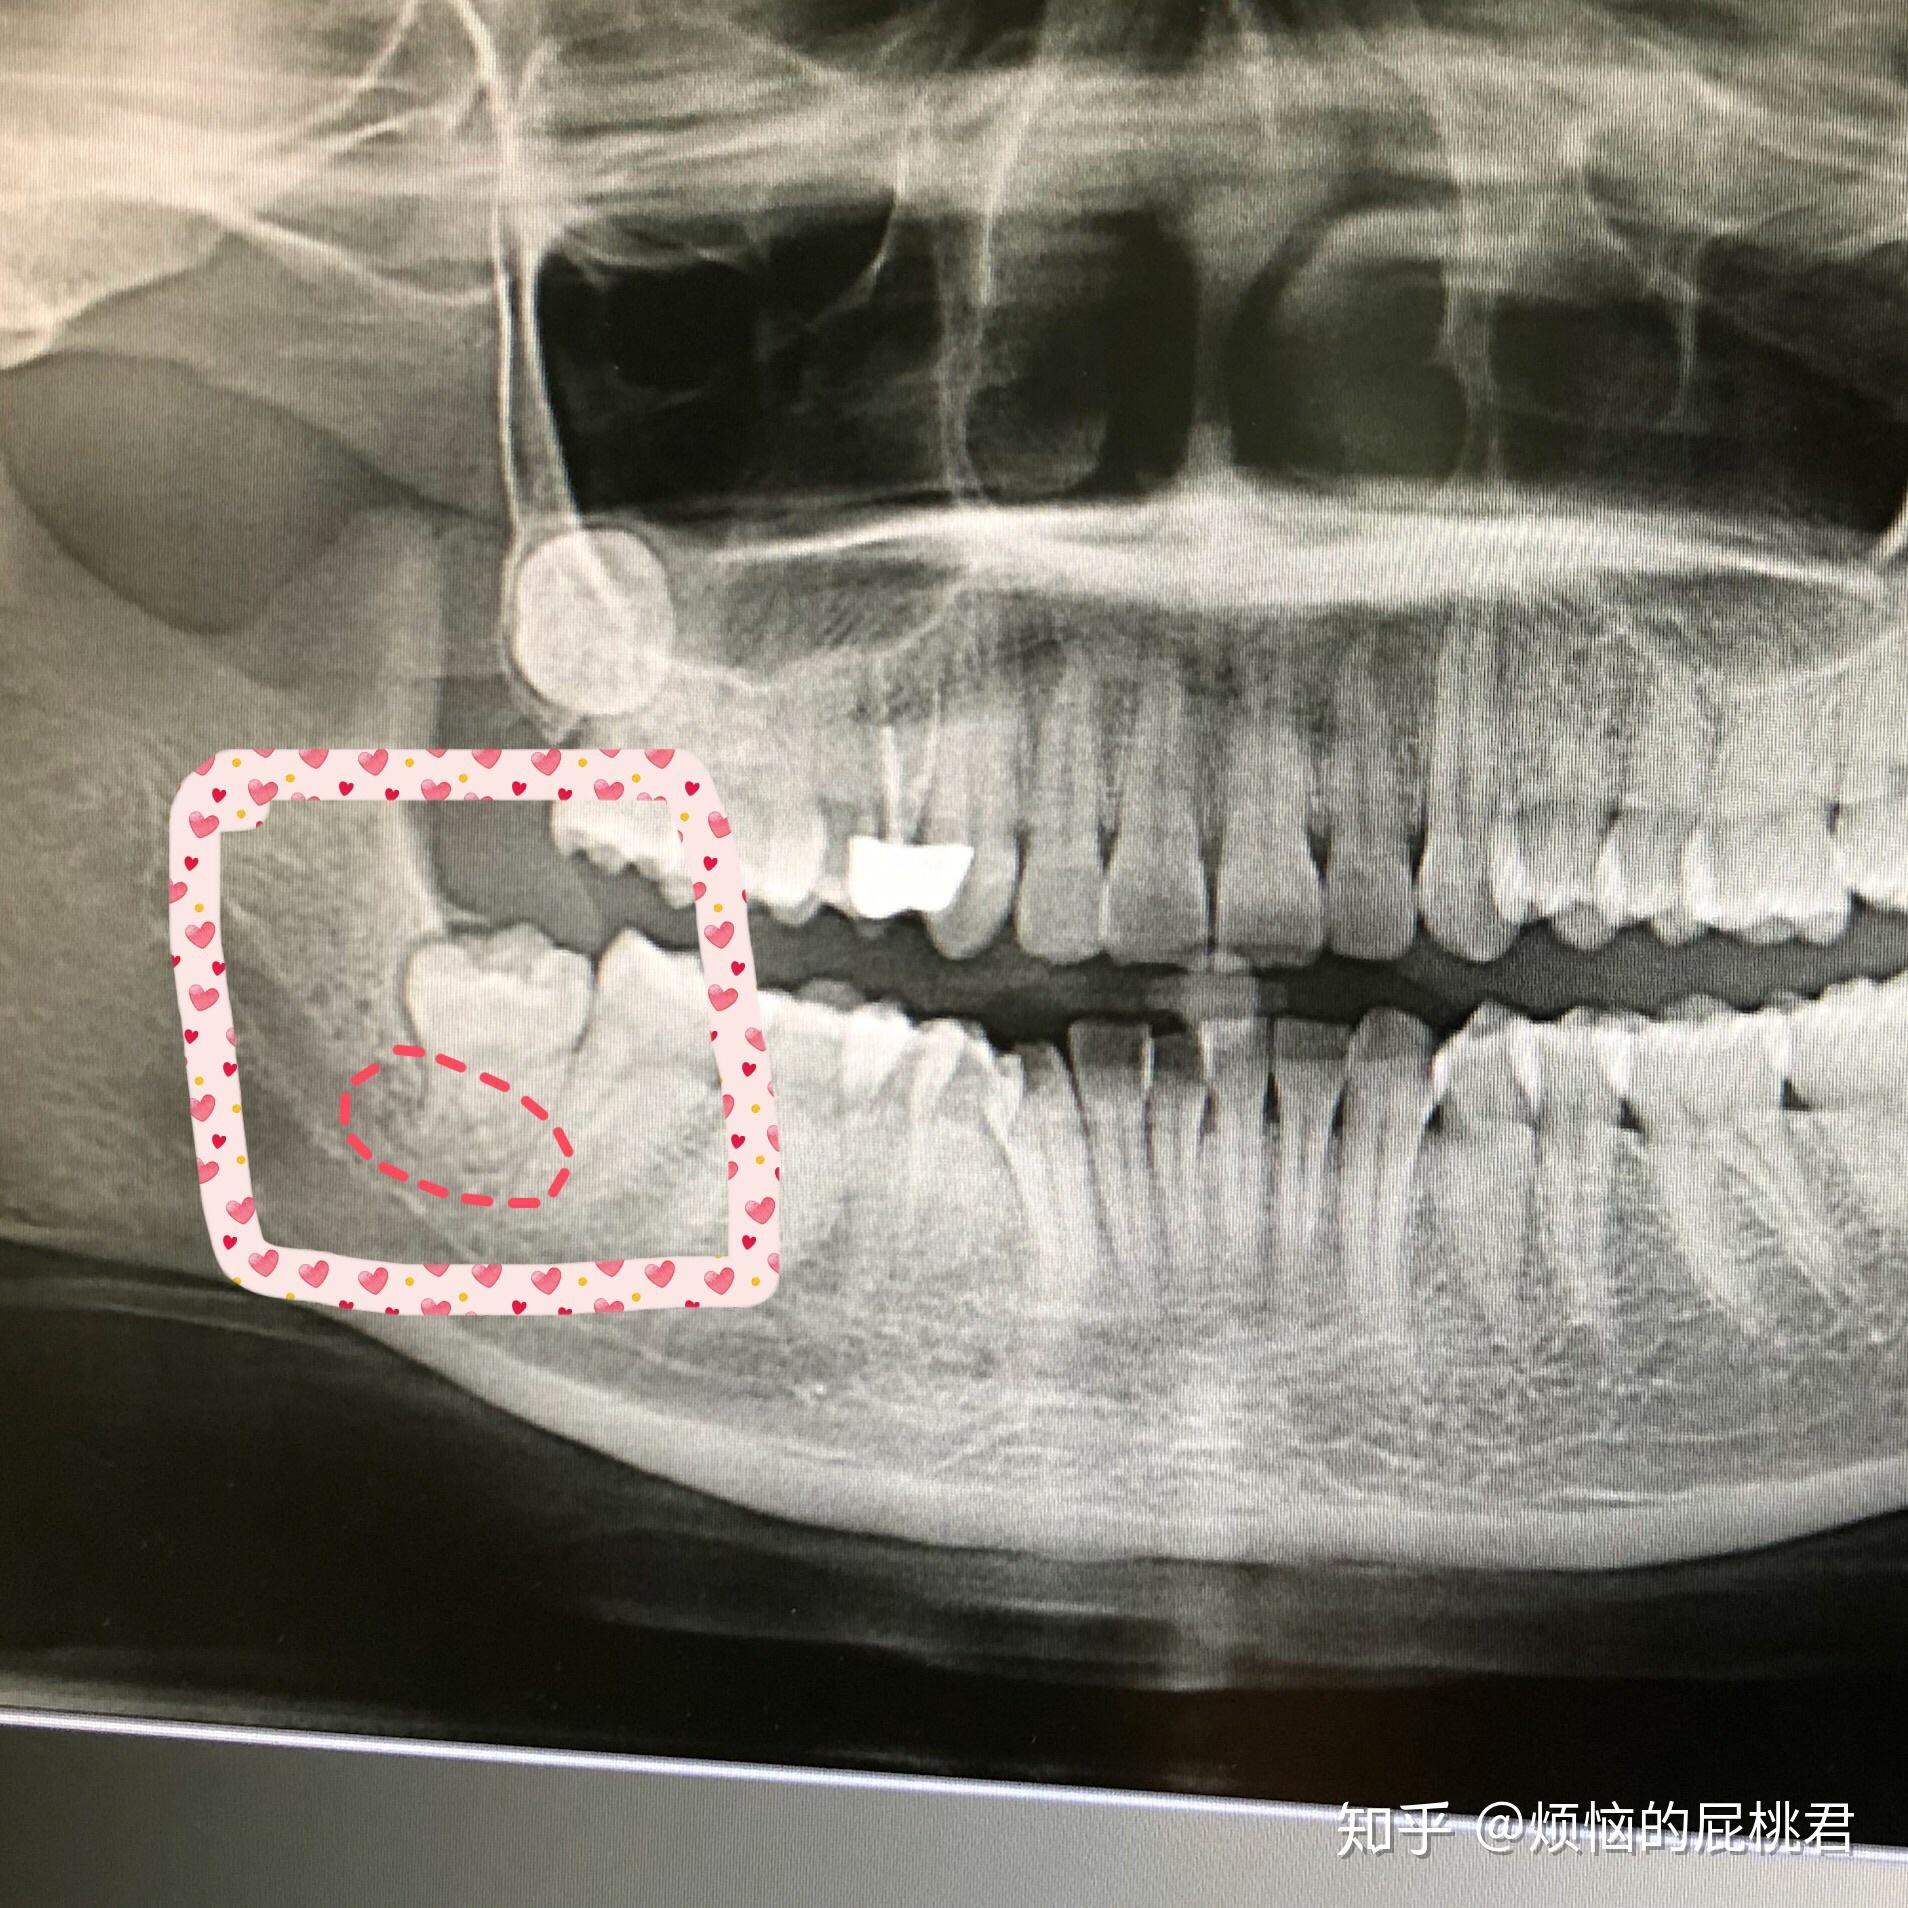

有没有姐妹拔过智齿,你们神经线距离牙齿多远啊,.

请问我这个智齿牙是否在神经上,拔掉有多少风险?谢谢了!

智齿跟在神经里,应该拔还是不拔?

智齿牙根离牙神经近拔的话风险会不会很大